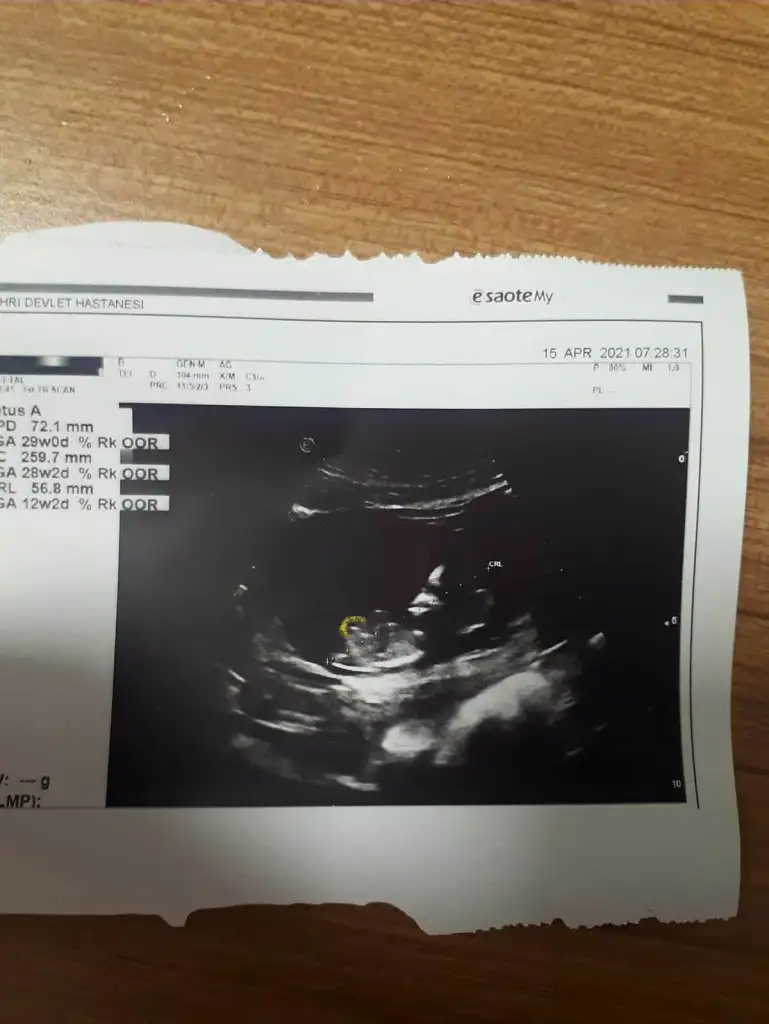

benimkini de yorumlar misiniz 11 haftalikErkek sanki

Erkek gibi sanki olursa 12-13 hafta paylaşın sizinmi kızınız vardı dimi11 haftalik benimkini de yorumlar misiniz

Bizede bakarmısın 12 haftalık bebeğimKız görünüyor

Nubu göremedim varsa USG paylaşın sanki kız tipi varBizede bakarmısın 12 haftalık bebeğim